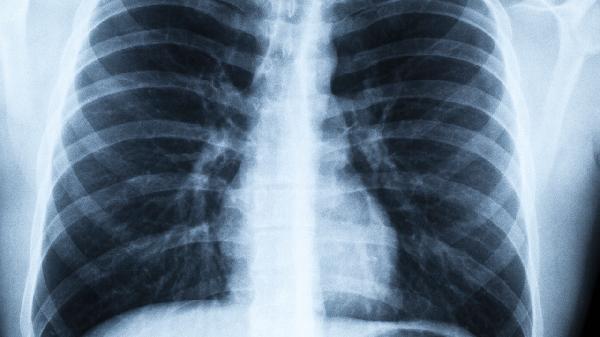

肺炎性肉芽肿通常不会癌变,属于良性病变。 肺炎性肉芽肿是肺部慢性炎症反应形成的局限性结节样病变,主要由结核分枝杆...

肺炎性肉芽肿通常不会癌变,但长期慢性炎症刺激可能增加恶变风险。 肺炎性肉芽肿是肺部慢性炎症引起的良性病变,主要由...